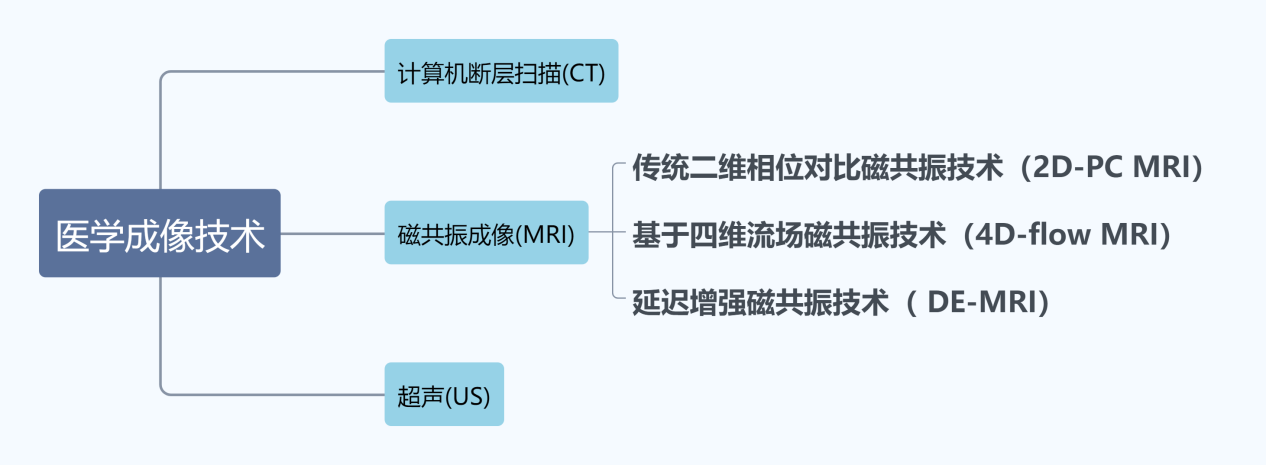

心房颤动(atrial fibrillation,AF)是临床常见的心律失常之一,具有较高的致残率和致死率。目前为止,影响因素的多样性和测试方式的差异性,导致我们很难理解心颤真正的机制和原理。那么,我们在科学上应该如何探讨这个研究?本项目主要由中国科学院深圳先进技术研究院的Kelvin Wong研究员团队与四川大学华西医院的朱达医师的团队合作开展,研究内容框架如图1所示。

图1 齿轮架构图为Kelvin Wong团队研究内容框架

心脏结构重构检测技术

图3 医学成像技术分类

MRI是利用核磁共振原理,依据能量在不同结构环境中不同的衰减情况,在外加磁场内,用探测器检测信号并输入计算机,经过转换处理在电脑上显示图像。由于其具有良好的软组织对比分辨率、扫描视野大、可获得各方位和角度的斜断面图像等优点,成为主流医学成像方式。与CT成像相比,MRI成像清晰且无辐射,在某些组织和部位成像显示更明显,不易产生噪声干扰,无需介入即可成像;与US成像相比,MRI成像更清晰,噪声影响小,在分割方面表现更好。图3从左至右依次是MRI成像图、CT成像图和US成像图。从图3中可以看出超声图像质量差,CT图像质量有所改善,但CT对人体有伤害,MRI成像清晰且对身体伤害较小,所以一般临床上更倾向于使用MRI作为临床诊断标准。